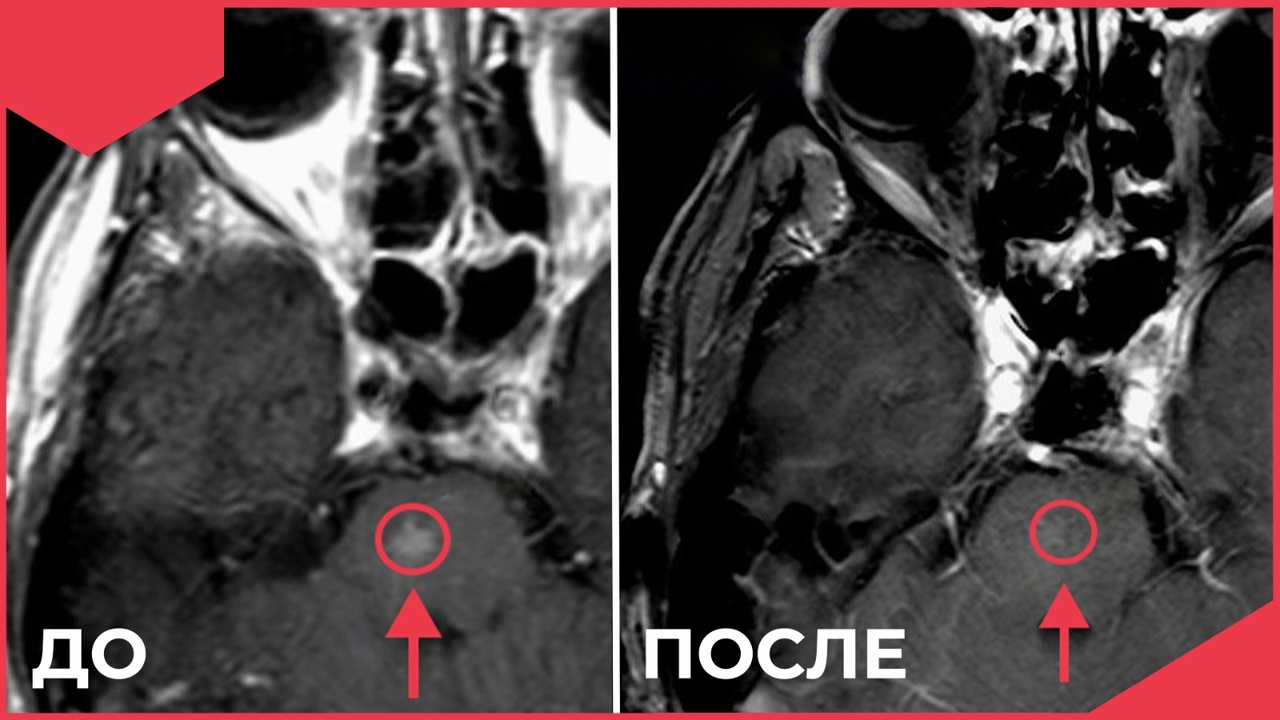

Во Владимирском онкодиспансере рассказали о применении новейших методов радиохирургии

С его помощью удаётся достичь высокой точности облучения сразу нескольких метастазов в головной мозг. Один из сложнейших методов лучевой терапии применяется в мире только с 2018 года и хорошо себя зарекомендовал. Как заверяет региональный Минздрав, пациенты Владимирской области, кому показан такой метод облучения, получают его в онкодиспансере по полису ОМС без квот, переездов и длительного ожидания.

фото: Минздрав области